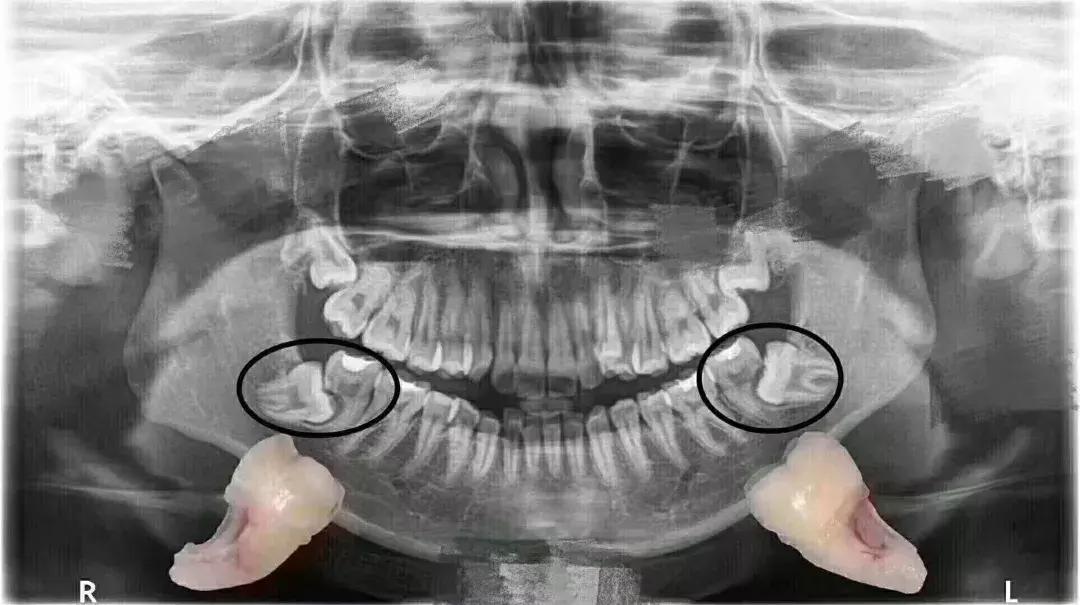

颌骨空间不足,引起的邻牙牙根吸收

如果说倒在第二磨牙上被龋坏的智齿还能抢救一下,像这样牙根都被「吃」掉的,就完全没救了。

最后不得不一拔拔俩↓